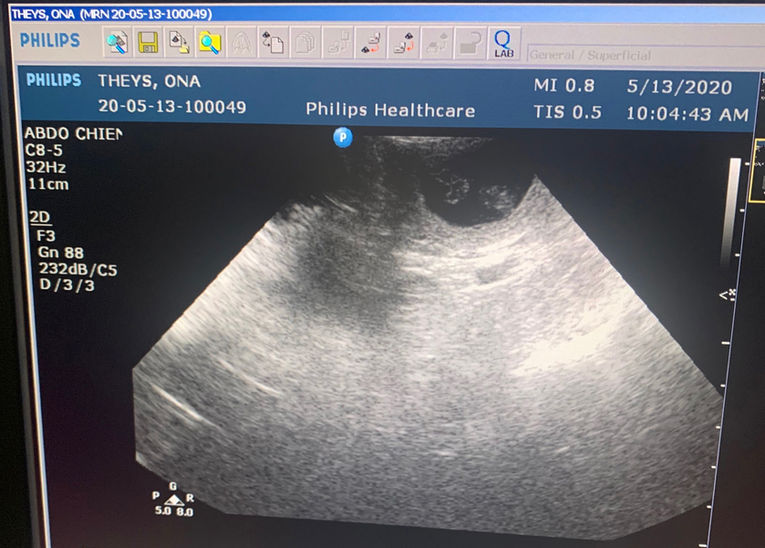

L'échographie de contrôle et la radio de Comptage

Le 13 mai nous avons eu le rendez-vous pour l"échographie de contrôle, nous avons eu l'occasion de voir quelques ovules fécondés. Comme nous procédons à une radio de comptage une semaine avant la mise bas, nous n'avons pas plus insisté.